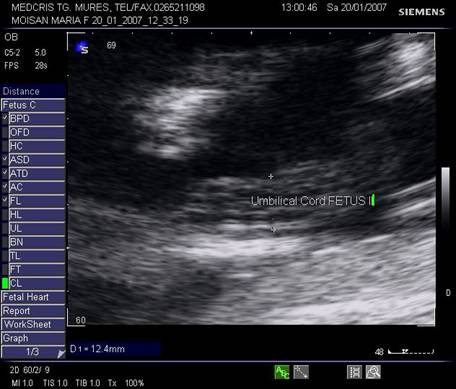

Fig nr 49. Sarcina 19 sapt. ,cu tripleti , biamniotica bichoriala, cu sindrom transfuzor transfuzat la fetii monoamniotici, cu retard de crestere intrauterina si cordon ombilical cu diam . pe jumatate la transfuzor ( intre cele doua calipere ) fata de transfuzat ( fig urmatoare )

Fig nr 50. Cordonul ombilical al fatului transfuzat , dublu fata de cel al transfuzorului, in diametru ( intre calipere )